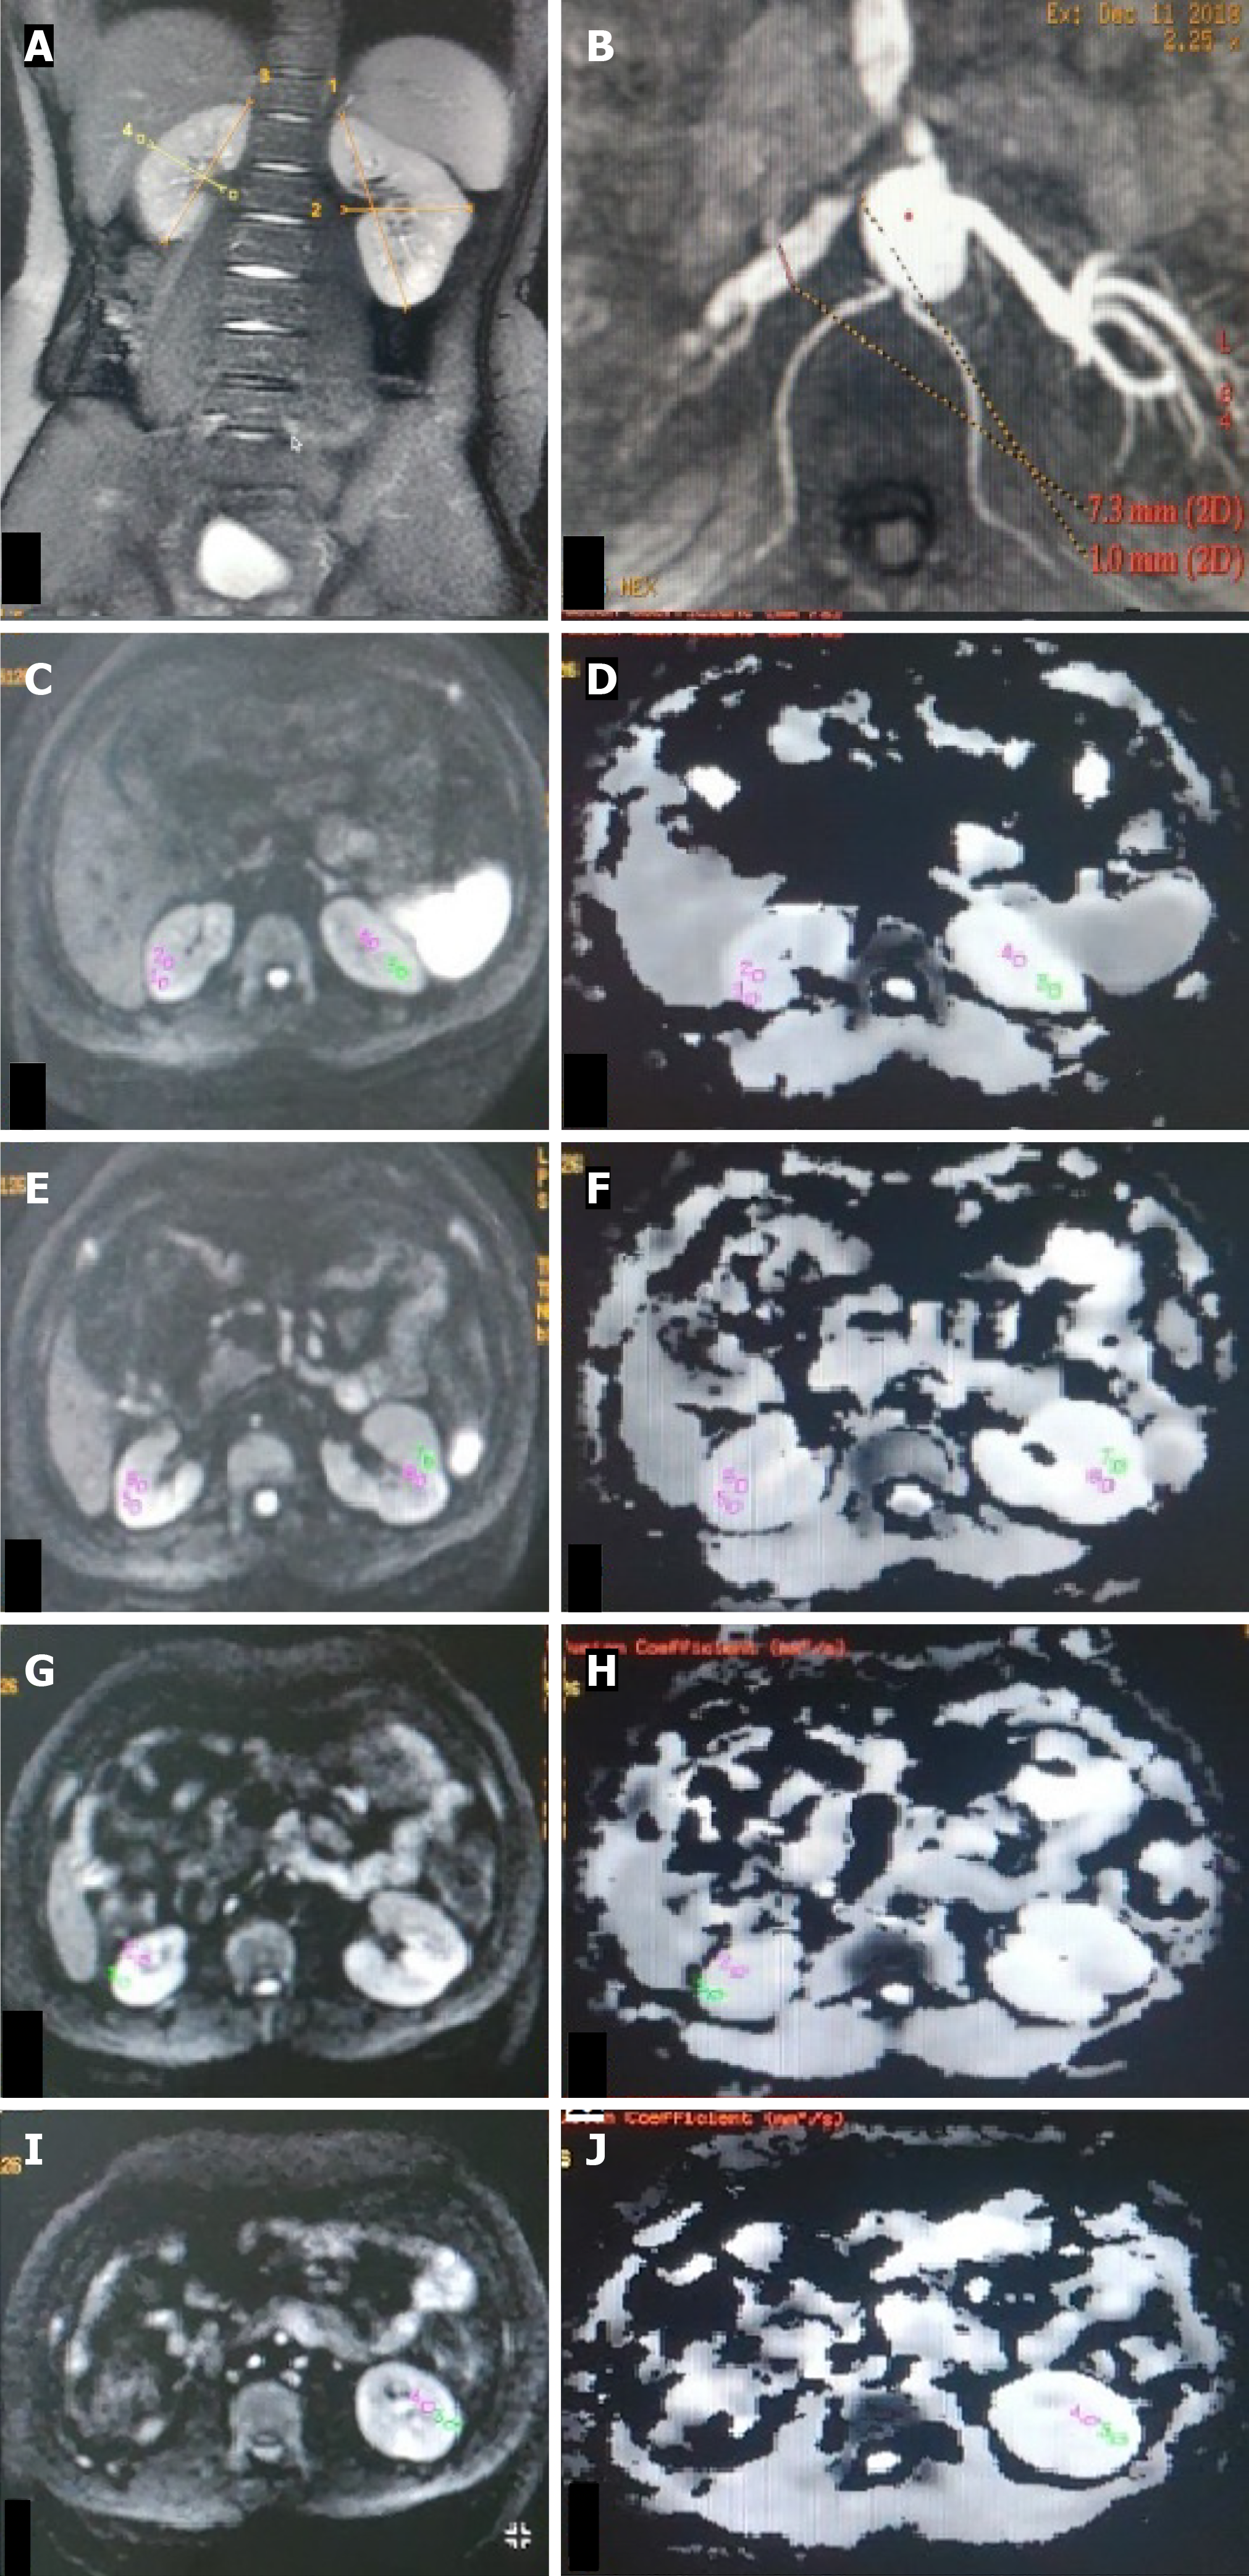

Figure 2 Bilateral renal artery stenosis.

A: T2W magnetic resonance (MR) image (coronal plane) showing atrophic right kidney (6.1 cm) and normal-sized left kidney (9.0 cm); B and C: Non-contrast MR angiography (INHANCE) in axial plane depicting diffuse stenosis of the right renal artery (B) and severe stenosis of the left renal artery at the ostium (C); D-I: Diffusion-weighted MR imaging (DW-MRI) image (D, F, H) in the axial plane with corresponding ADC map (E, G, I) of bilateral kidneys showing manually drawn region-of-interest (ROI) placed in the upper (D, E), middle (F, G) and lower (H, I) pole regions of the bilateral kidney. On the right side, as the kidney is atrophic, the ROI was placed in the corticomedullary region, whereas on the left, the ROI was placed separately in the cortex and medulla. Mean corticomedullary ADC of the right kidney was 1.19 × 10-3 mm2/s. Mean cortical ADC and medullary ADC values of the left kidney were 169 × 10-3 mm2/s and 1.76 × 10-3 mm2/s, respectively.